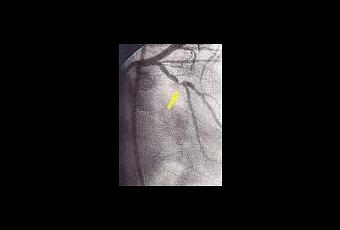

Pour continuer mon histoire, J'ai essayée de lui parler de Zamboni, de sa théorie de et des 12.500 Libérés de la Insuffisance Veineuse Cérébro-spinale Chronique à travers le monde, mais elle m'a dit que sa mère avait parlée a son neurologue de Zamboni, mais .... son neurologue est un neurologue et il fait ... le neurologue ... Pour avoir ma conscience tranquille je essayée de lui expliquer que 90% des malades de scléroses en plaques on aussi l' Insuffisance Veineuse Cérébro-spinale Chronique ( par contre le 2% des personnes saines on ça!) que un semple eco-color-doppler ça suffit pour détecter çà ... elle ma clouée le bec en me disant que dans sa famille il y avait des médecins ... !!!???

Le but de ce site est de vous donner des informations (si possible en français) sur l'Insuffisance Veineuse Cérébro-spinale Chronique et ses liens possibles avec la Sclérose en Plaques.

A ce jour, le nombre d'intervention pour IVCC dépasse 12.500 à travers le monde ! Témoignages: http://www.ivcc.fr/temoignages.html